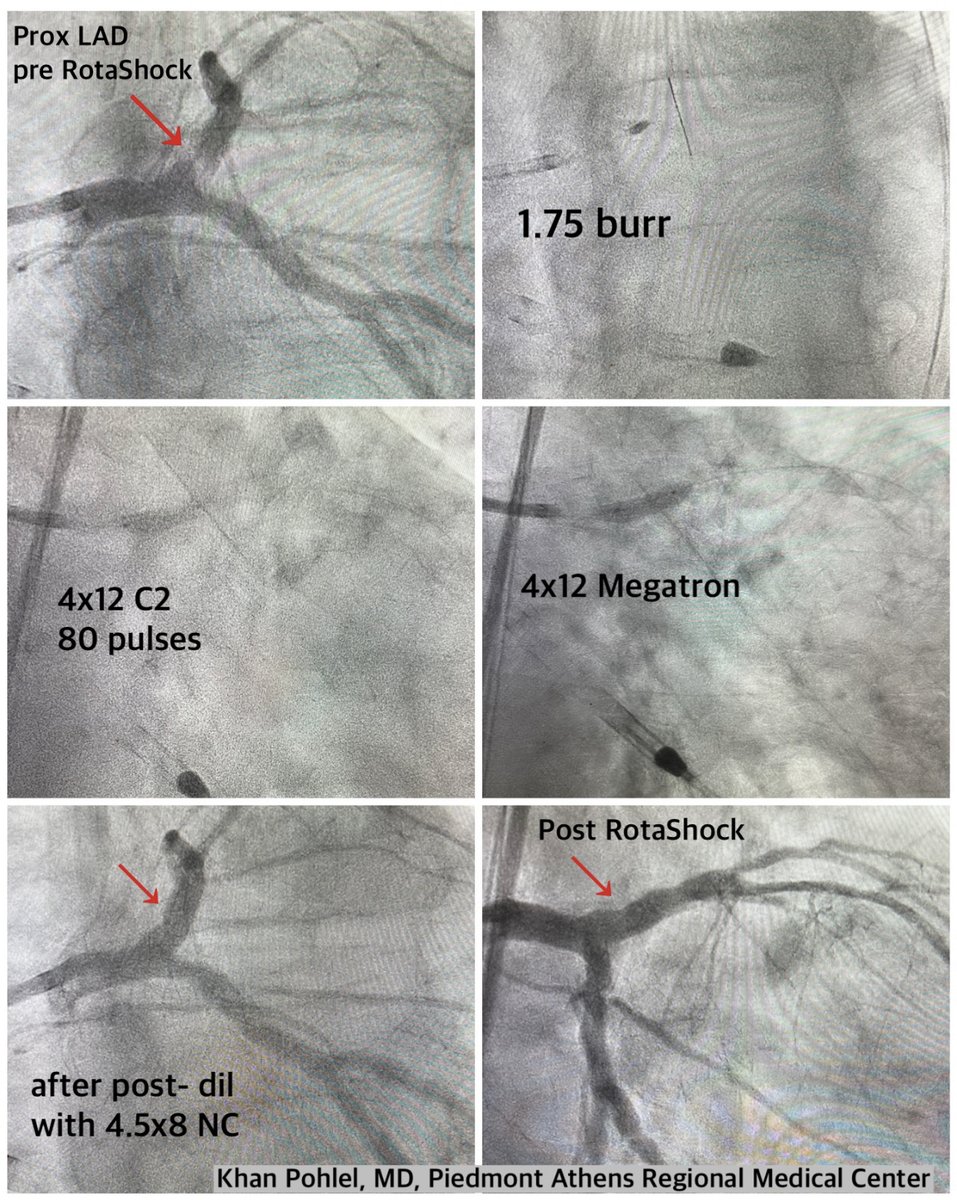

Dr. @KPohlel of @PiedmontHealth Athens Regional faced an unyielding LAD. Unable to cross the lesion the prior day, he switched to the #RotaShock technique, crossing the lesion with a 1.75 rota burr and then cracking the calcium with 4.0 #ShockwaveC2. ISI bit.ly/3iEq7fC

ShockwaveIVL's tweet image. Dr. @KPohlel of @PiedmontHealth Athens Regional faced an unyielding LAD. Unable to cross the lesion the prior day, he switched to the #RotaShock technique, crossing the lesion with a 1.75 rota burr and then cracking the calcium with 4.0 #ShockwaveC2.